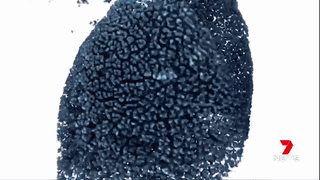

澳洲的科學(xué)家們通過運用納米技術(shù),將“基因沉默”(gene silencing)藥物運送至腫瘤細胞中來治療胰腺癌。

藥物已經(jīng)在擁有和人類相仿的瘢痕組織的小鼠身上進行試驗,并獲得成功。